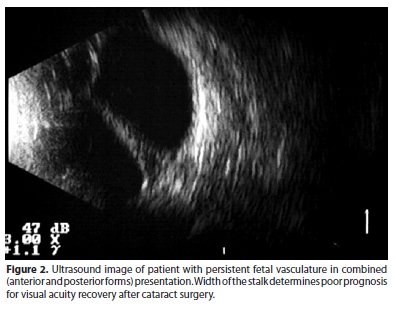

New studies concerning cumulative factors that could predict prognosis for each case are necessary to help ophthalmologists to decide whether to perform surgery. Among the main pre-operatory clinical variables are: lens and vitreous opacities affecting the visual axis (Figure 1), width and occurrence of blood flow inside de stalk detected by eco-Doppler (Figures 2 and 3), retrolental vascularized plaque also detected by eco-Doppler (Figure 4), form of PFV presentation with major or minimal macular involvement (Figure 5), presence of microphthalmia and patient's age at surgery.

The prognosis after cataract surgery seems to be linked to the presentation forms of the PFV and associated preoperative ocular features. Anatomical results depend on the fibrovascular stalk width, presence of blood flow inside the stalk, type of presentation (anterior, posterior or combined form of PFV) and associated microphthalmia. Those variables are associated with the higher incidence of postoperative complications. Visual and functional results depend on age of lens opacity occurrence (congenital or latter acquired cataract formation), age at surgery and presence of major or minor macular involvement.